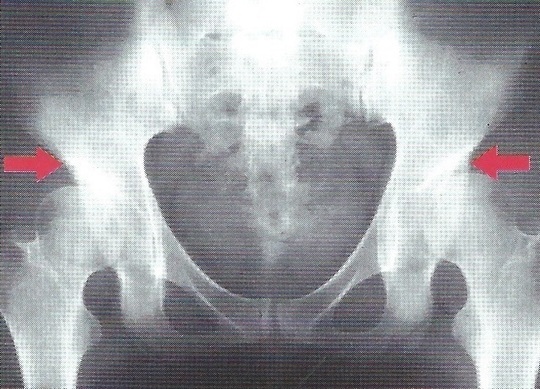

はじめに関節軟骨がすり減り始め、最後には骨の変形をきたします。

骨のう胞

【診断】

問診、股関節の誘発痛可動域制限、X線像などで判断します。

変形性股関節症